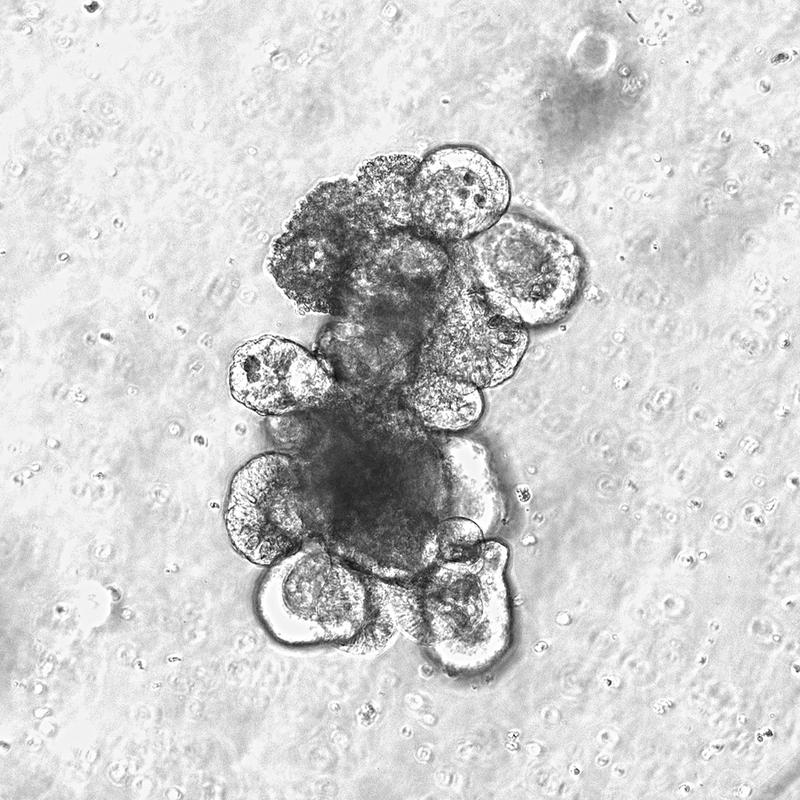

Kleine „Mini-Därme“: Moderne Organoidkulturen helfen bei der Analyse

Die Wissenschaftler untersuchten Gewebeproben von Patienten nach Stammzelltransplantation sowie verschiedene Mausmodelle für strahlen- und therapieinduzierte Darmschäden. Zusätzlich nutzten sie moderne Organoidkulturen - kleine „Mini-Därme“, die im Labor aus menschlichen Stammzellen gezüchtet werden - , um die Wirkung des bakteriellen Stoffwechselproduktes auf die Darmschleimhaut gezielt zu analysieren.